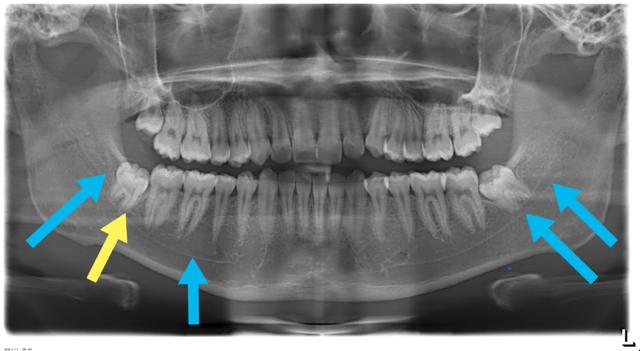

(绿色箭头指的是下牙槽神经管,黄色箭头指的是牙根,两者有重叠,须加拍cT)

(截冠半年后牙根已经离开神经管,这时候拔掉牙根很安全)